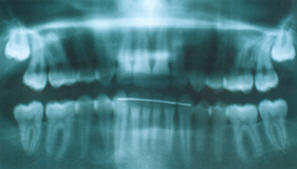

B) Telerradiografía

de perfil.- previo al inicio del tratamiento

B) Fig.

4.-Telerradiografía de perfil, previo al inicio del

tratamiento |

Las medidas

cefalométricas revelaron un ángulo SNA de 83º, un SNB de 77.8 y un

ANB de 5.2º, el ángulo interincisivo tiene 137º, y el incisivo

inferior en relación a APg. Esta a -2 mm, la Base Craneal Posterior

muy grande 41 mm. (fig. 5 y en cefalogramas presentados al final de

esta descripción, antes y al final del tratamiento)